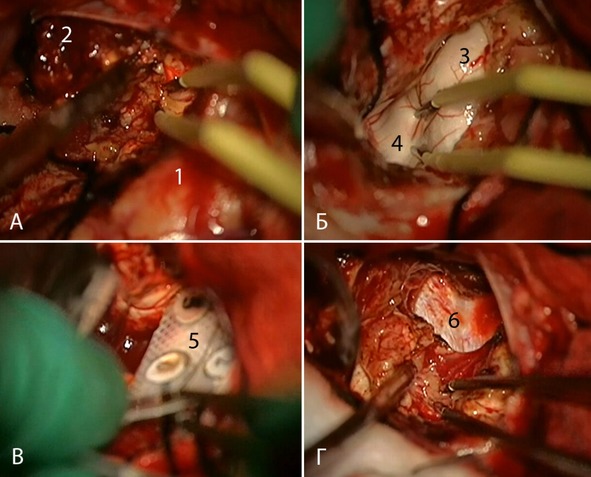

Выполнено удаление каверномы правой височной доли в сочетании с передней лобэктомией и амигдалогиппокампэктомией (рисунок 32).

Рисунок 32. Клиническое наблюдение №5. Интраоперационные фотографии больного Б. Лобно-височная трепанация справа, резецированы передние отделы правой височной доли (1). А – удаление каверномы (2). Б – доступ в полость височного рога бокового желудочка, цифрами отмечены передние отделы гиппокампа (3), хориоидальная щель (4). В – Укладка электрокортикографического электрода (5) вдоль гиппокампа. Г – субпиальная резекция гиппокампа, 6 – твердая мозговая оболочка дна средней черепной ямки.